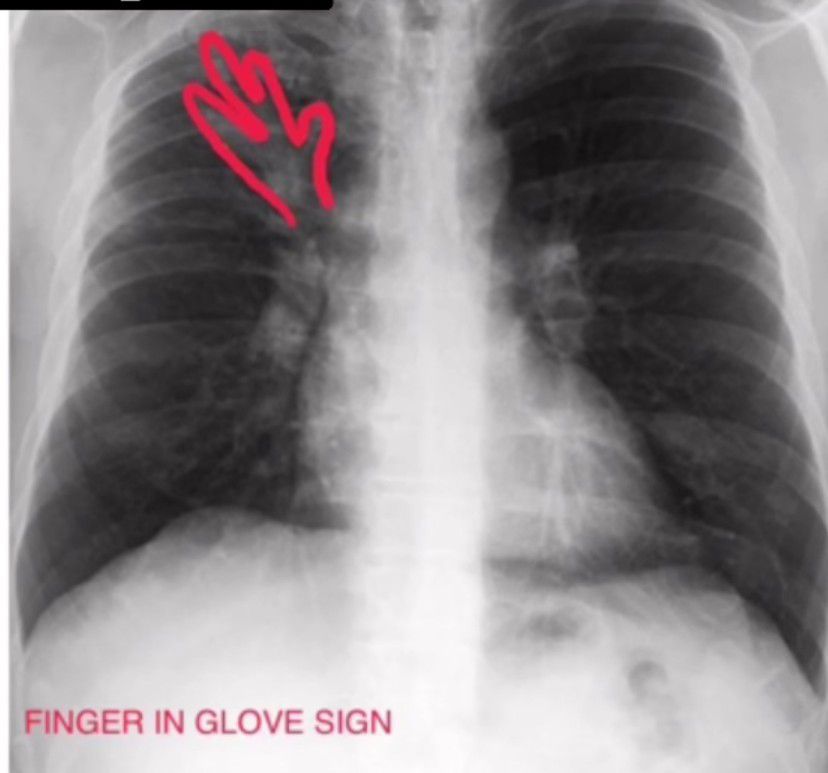

Finger in Glove Sign

The finger-in-glove sign is a radiographic feature and refers to mucoid impaction in central airways and typically radiates from the hilum to the periphery. Mucoid impaction is defined as airway filling by mucoid secretions.